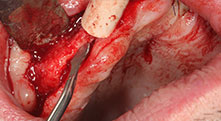

Piezomed B6

La cresta alveolare è stata incisa su entrambi i lati tramite piezochirurgia (strumento utilizzato: Piezomed B6). Gli impianti sono stati posizionati con la stessa procedura e l'osso peri-implantare è stato costruito con la tecnica GBR.

Potrebbe descrivere in breve, ad esempio, la procedura che utilizza per fare spazio ai blocchi ossei per il trapianto?

Bratu: Preferiamo prelevare l'osso dalla cresta esterna obliqua della mandibola posteriore, non dalla regione interforaminale. Dopo l'incisione del tessuto molle, utilizziamo le nuove seghe ossee per definire la quantità di osso da prelevare. Quasi nell'80% dei casi adottiamo lo stesso approccio, quindi utilizziamo le seghe ossee, anche per l'intera preparazione. Potremmo utilizzare anche altri strumenti piezochirurgici e, al termine, un bisturi per far spazio al blocco. Secondo noi, si tratta di una tecnica chirurgica molto efficace.